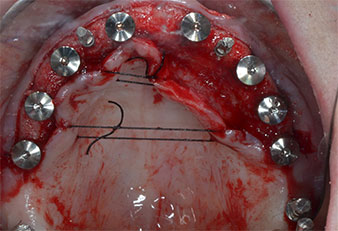

Поради сравнително твърдата кост (D2) в тази област, 10-милиметровото имплантно ложе в позиции 11 и 21 беше завършено с ротационен дрил с диаметър 4 mm в комбинация с W&H хирургичен обратен наконечник WS-75 L, W&H имплантологичен мотор Implantmed и опционалния W&H Osstell ISQ модул. За разлика от това, благодарение на меката кост, дисталните зони се подготвят до окончателен диаметър 3 mm, използвайки накрайник за Piezomed I3P. Имплантите най-накрая са поставени трансгингивално, за да остеоинтегрират за три месеца (Фиг. 6-10). Съществуващата протеза се фиксира на четирите временни импланта (Фиг. 8).